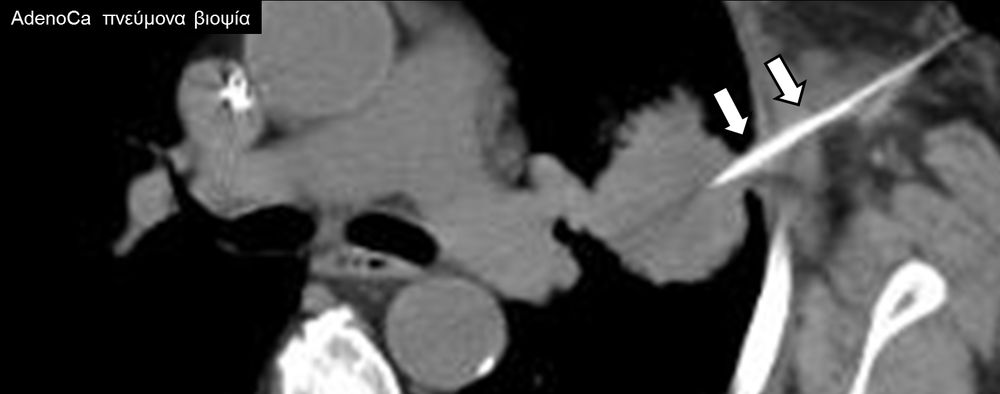

Η διαδερμική βιοψία είναι μία ελάχιστα επεμβατική μέθοδος λήψης υλικού από τον όγκο για κυτταρολογική και ιστολογική εξέταση, από εστιακές αλλοιώσεις του ήπατος, πνεύμονα, νεφρού κλπ. Συστήνεται από τον κλινικό ιατρό ανάλογα με το είδος και το μέγεθος της βλάβης και πραγματοποιείται με ασφάλεια από επεμβατικό ακτινολόγο με την καθοδήγηση αξονικού τομογράφου ή υπερήχων. Στη σύγχρονη ογκολογική θεραπεία όπου γίνεται προσπάθεια καταπολέμησης του καρκίνου σε μοριακό επίπεδο κρίνεται αναγκαία η ακριβής ιστολογική ταυτοποίηση του όγκου ώστε να εφαρμοσθεί εξατομικευμένη θεραπεία για το βέλτιστο αποτέλεσμα. Οι κατευθυνόμενες βιοψίες στοχευουν στο να παρέχουν στον κλινικό ογκολόγο το απαραίτο ιστοπαθολογικό υλικό που θα του επιτρέψει να εφαρμόσει την κατάλληλη θεραπεία για τον ογκολογικό ασθενή.